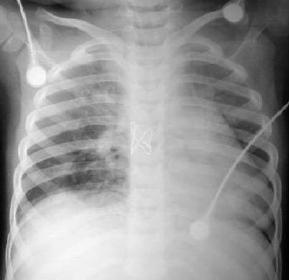

Radiología Pos – Operatoria

La radiografía pos operatoria inmediata muestra un corazón en posición lateral izquierda, pero evidentemente mas centrado, observe que la imagen radiolúcida en el sitio donde estaba la depresión esternal ya no existe, para que regrese la imagen cardíaca completamente requiere de tiempo, en la vista lateral obviamente se aprecia la corrección external, con franco desplazamiento anterior de la silueta cardiaca.